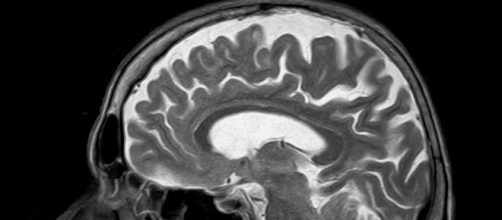

A functional Magnetic Resonance Image (fMRI) is a non-invasive brain scan which shows what parts of the brain are most active by measuring blood flow to those regions. One researcher said, “The first thing that struck us was just how good everyone’s memory was,” because on average they remembered so well that they talked about the episode for almost half as long as the entire episode lasted or more than 20 minutes, even discussing Sherlock’s hat.

But the real surprise was that when they compared the brain images during watching and later during remembering. They were nearly identical; so much so that researchers could identify what scenes the subjects were describing just from comparing the fMRI scan patterns with those taken during the viewing.